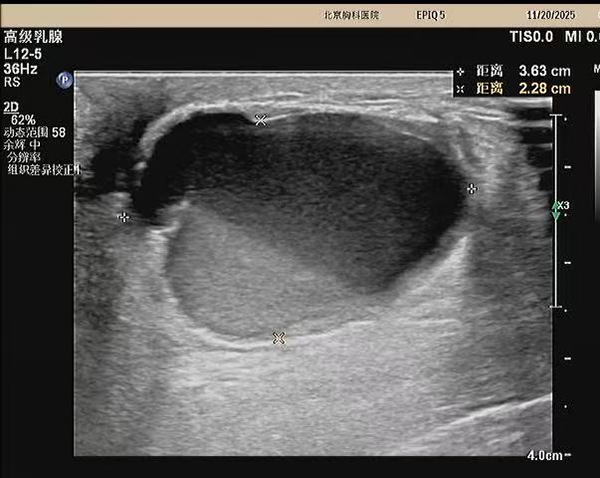

据悉,该患者三个月前自查发现左侧乳房有一质硬肿块,虽无红肿热痛等典型症状,但因担忧恶性病变而长期处于焦虑状态。就诊后,超声医学科主任王金萍迅速为其安排检查。超声影像显示:左乳3点位存在一大小约3.6×2.3厘米的混合回声包块。凭借丰富的临床经验,王金萍判断该病变为良性液性病灶,具备明确干预指征且无恶性风险。

在充分沟通并取得患者同意后,王金萍为患者实施了超声实时动态引导下的穿刺抽液术。术中精准定位病灶,顺利抽出白色糊状液体,并辅以生理盐水灌洗,使包块基本消失。整个过程患者无任何不适,术后即刻离院,情绪明显改善。后续病理结果证实:未见癌细胞,进一步打消了患者的顾虑。